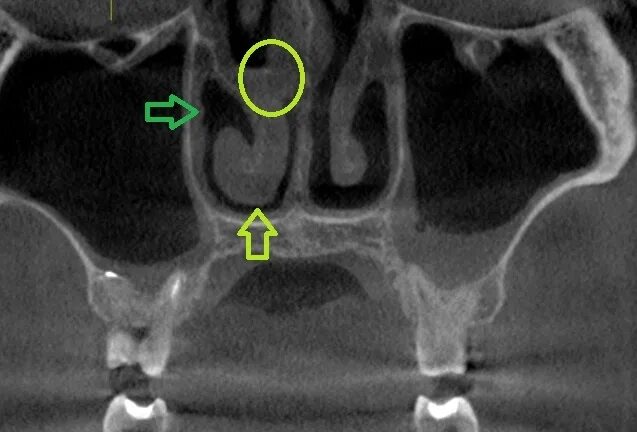

Как лечить утолщение слизистой верхнечелюстной пазухи